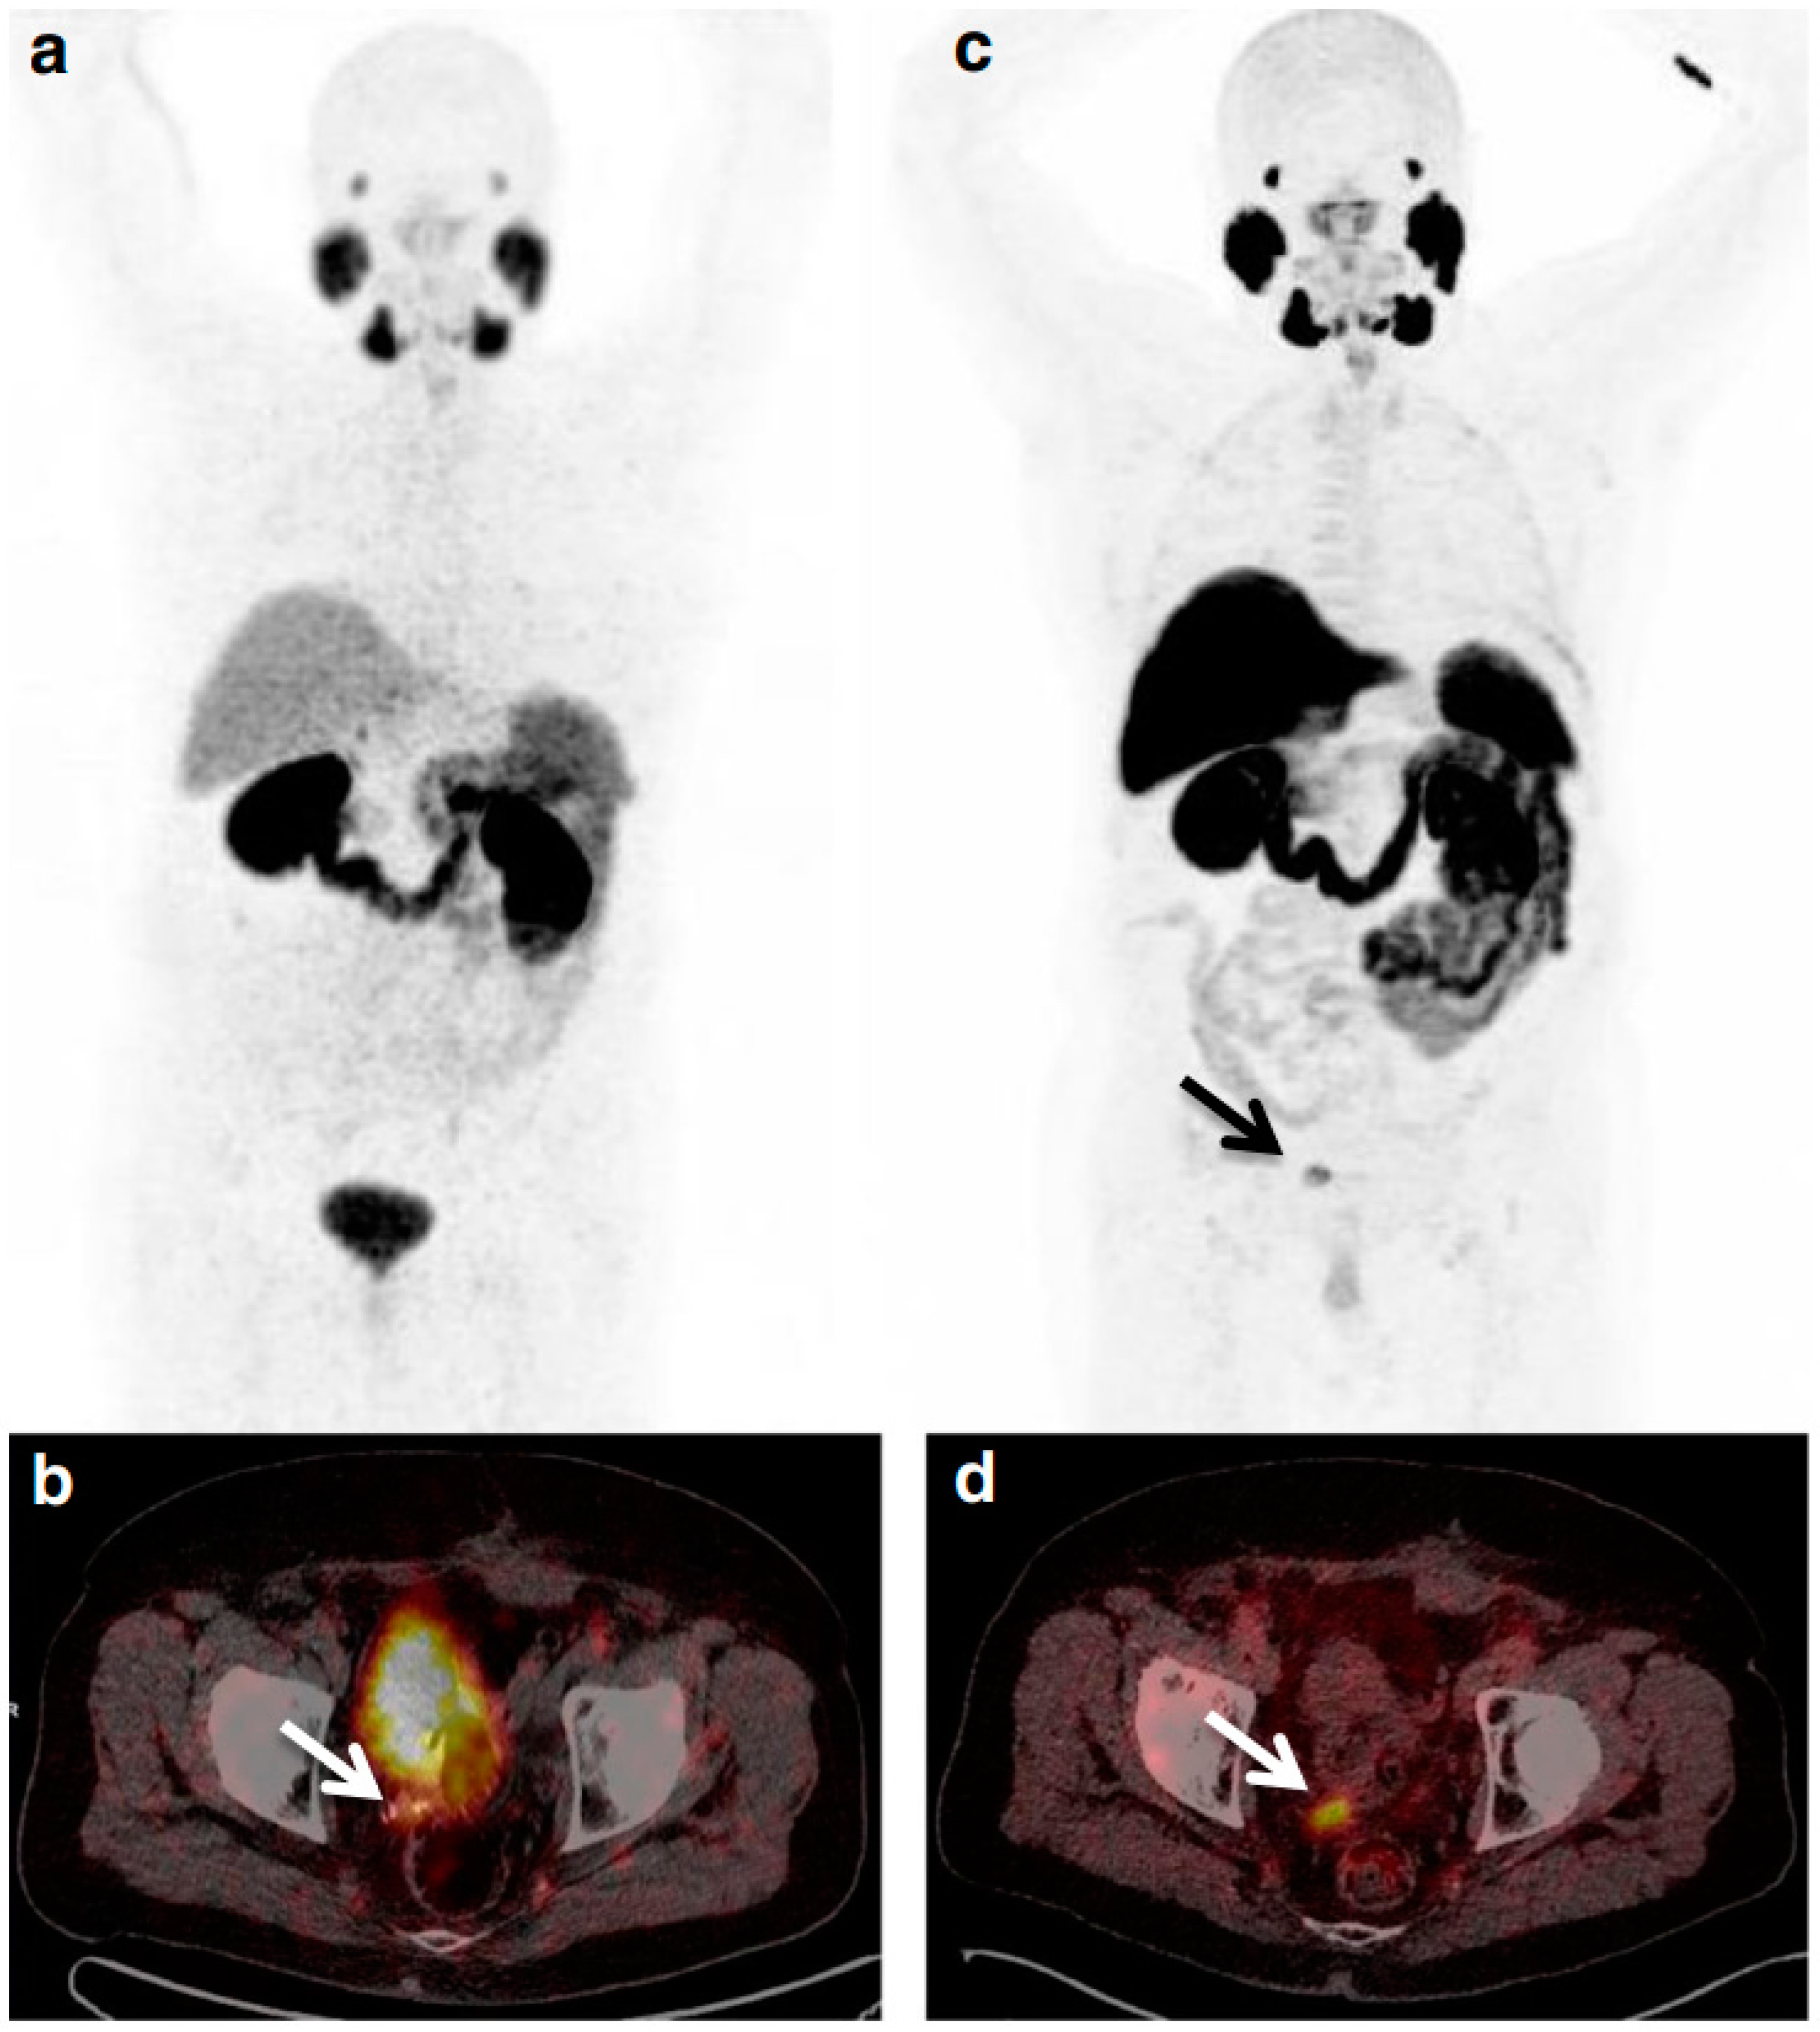

- Rahbar, K.; Weckesser, M.; Ahmadzadehfar, H.; Schäfers, M.; Stegger, L.; Bögemann, M. Advantage of 18F-PSMA-1007 over 68Ga-PSMA-11 PET imaging for differentiation of local recurrence vs. urinary tracer excretion. Eur. J. Nucl. Med. Mol. Imaging 2018, 45, 1076–1077. [Google Scholar] [CrossRef]